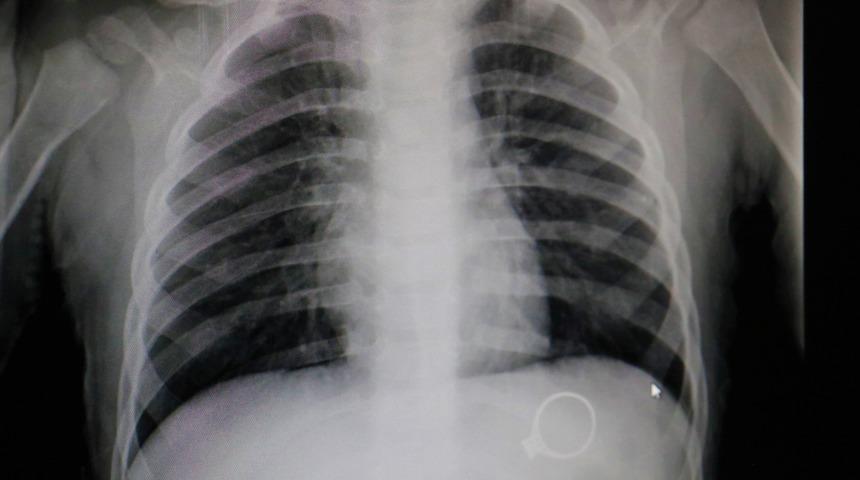

Sivas'ta kent merkezinde yaşayan F.G. ve C.G. çiftinin 1.5 yaşlarındaki M.G adındaki bebekleri oynamak için annesinden tek taş yüzüğünü istedi. Yüzükle oynayan M.G. annesine fark ettirmeden yüzüğü yuttu. Bir süre sonra çocuğunun yüzüğü yuttuğunu fark eden anne çocuğunu kucaklayarak hastaneye götürdü. Burada Çocuk Cerrahisi Uzmanı Op.Dr. Mahmut Aluç tarafından muayene edildi. Yüzüğün, röntgeni çekilen M.G’nin midesinde olduğu görüldü. 6 gün sonra yüzük doğal yollarla çıktı. Çıkan yüzük aileye rahat bir nefes aldırdı.

Çocuk Cerrahisi Uzmanı Op.Dr. Mahmut Aluç, çekilen röntgende yüzüğün midede olduğunu belirlediklerini ifade ederek, “Hastamız 1 buçuk yaşında. Bundan 6 gün önce bize yüzük yutma şikayeti ile başvurdu. İlk çektiğimiz grafide yüzüğün mide de olduğunu saptadık ve aileyi bilgilendirdikten sonra rutin prosedürlerinin gereği beklemeye başladık. 6 gün sonra spontane olarak yüzüğün kendisi çıktı. Bu tür hastalarla oldukça sık karşılaşıyoruz. Rutin olarak şöyle bir kural vardır, çocuk ağzına aldığı her şeyi yutabilir. Özellikle küçük çocuklar cisimleri tanımak için elleriyle dokunduktan sonra genellikle ağızlarına alırlar. Bu yutulan cisimler toplu iğne olabilir, çengelli iğne olabilir, para olabilir” dedi.